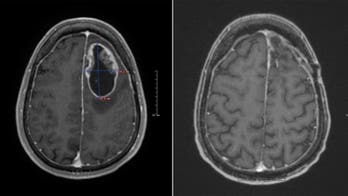

Brain Cancer - Page 9